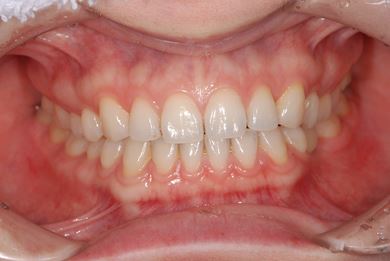

| 性別/年齢 | 女性 / 29歳 | ||||||||||||||||||||||||||||||||

| 主訴 | インプラント治療と、親知らずの抜歯の相談。なるべく安価で、短期間で終了して欲しい。 | ||||||||||||||||||||||||||||||||

| 治療方針 | 欠損部分をインプラント治療にて、機能的・審美的回復を行う。 | ||||||||||||||||||||||||||||||||

| 治療内容 | インプラント1本、メタルボンドセラミッククラウン1本 | ||||||||||||||||||||||||||||||||

| 総治療費 | 252,000円 | ||||||||||||||||||||||||||||||||

| 治療期間 | 11ヶ月 |